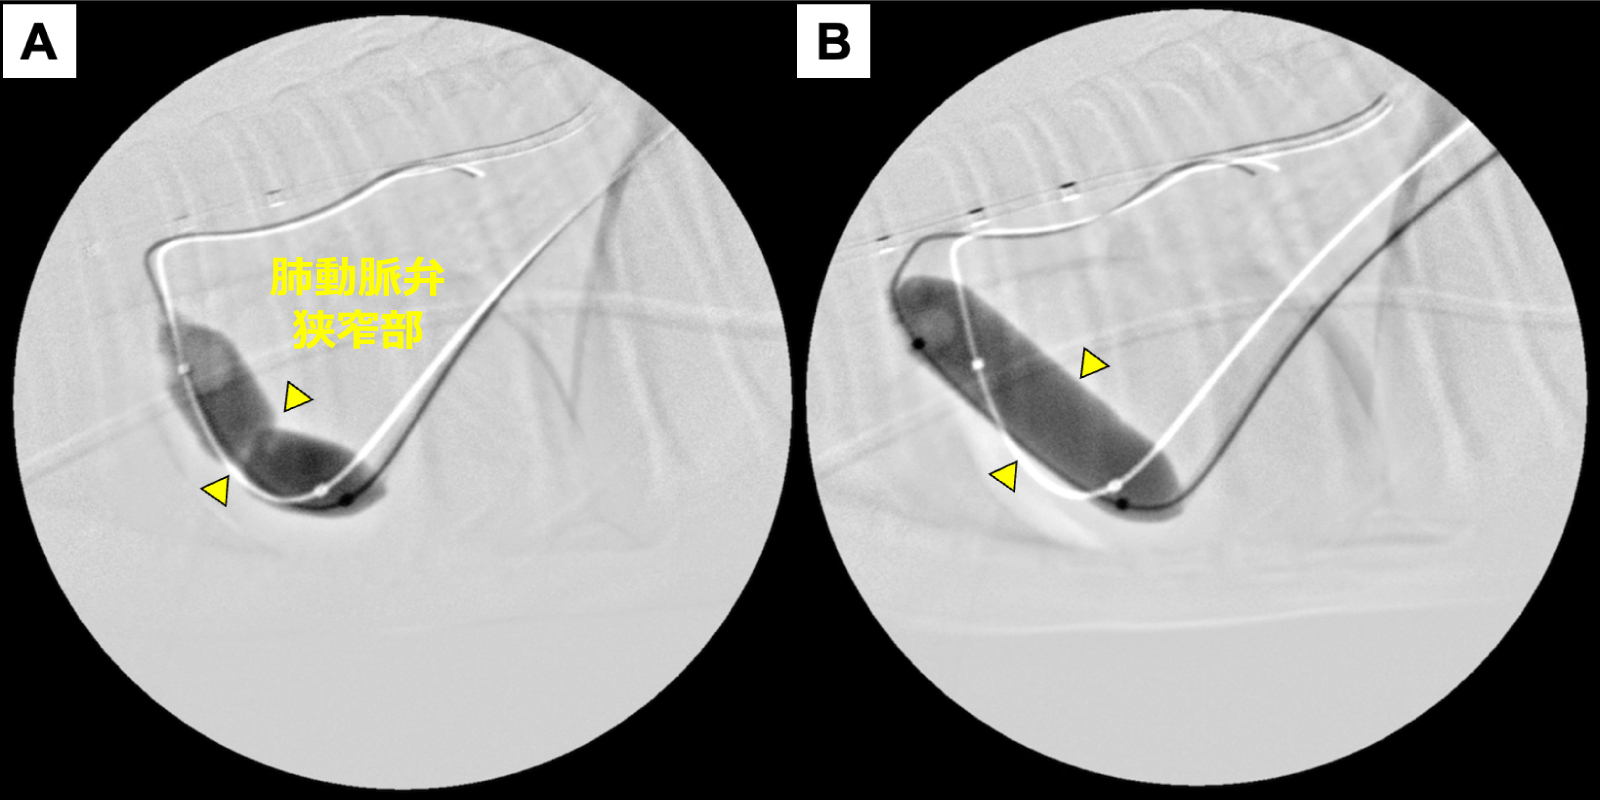

バルーンのスリッピングなどもなく、

狭窄部位に対するバルーンのくびれ消失を確認

ステント留置後、運動不耐性は改善された